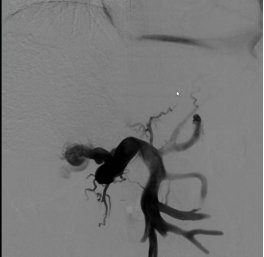

经过充分的术前准备,手术在我院杂交手术室进行。首先,黄纪伟教授、廖明恒副教授团队在下腹作一小切口,将肠系膜上静脉分支暴露;然后,吴浩教授、魏波副教授消化介入团队将特定的手术器械送入肠系膜上静脉,在肠系膜上静脉近门脉端与下腔静脉之间放置覆膜支架建立分流通道,类似于开闸泄洪,使部分淤滞的肠道、脾脏血流直接进入体循环,降低门静脉系统压力,控制和防止静脉曲张破裂出血,促进腹水吸收。

手术历时1+小时,过程顺利,术后肠系膜上静脉造影见支架分流通畅,门体静脉压力梯度由术前20mmHg降至术后8mmHg,手术达到预期目标。术后患者情况稳定,复查CT显示支架通畅,侧支循环消失,5天后好转出院。患者后续需要长期服药治疗包虫病灶。

(左图:术前CT重建 右图:术后CT重建)